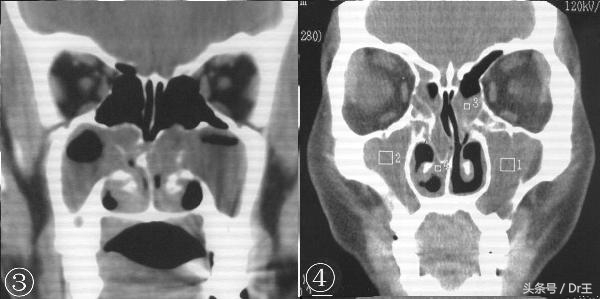

脸部骨头后方、头部中央有许多腔室(称为鼻窦),空气由鼻子吸入后进入鼻窦最后再进入气管连接到肺,鼻窦内黏膜会分泌黏液保持鼻窦湿润,并且阻挡细菌与灰尘进入肺。

鼻窦炎指的是鼻窦受细菌、病毒、霉菌、过敏原感染或因自体免疫系统而引起的发炎反应。